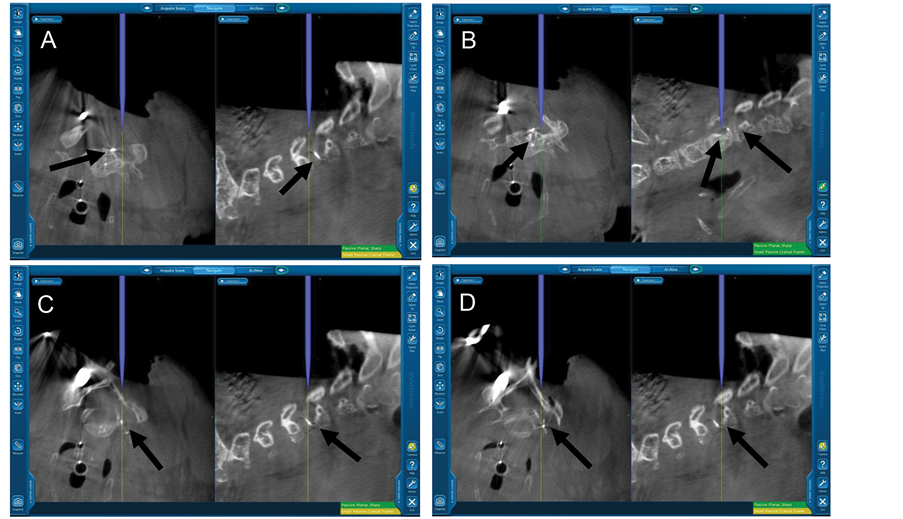

We used the image guidance to first define the residual bony anatomy under the dense scar tissue and trace the course of the embolized vessels. After exposing the remaining bone laterally on the right side from C5-T1, decompressive foraminotomies were performed in standard fashion to decompress the C6, C7, and C8 nerve roots. Intraoperative neuromonitoring was used during the procedure. The scar tissue and vascular malformation obliterated the typical dissection planes, and image guidance was utilized for continued reorientation. The previously embolized feeding vessel was identified using image guidance, and it was traced back to the vertebral artery (Figure 4). This established our boundaries for resection of the vascular malformation, which was removed with conventional microvascular surgical techniques. There were no major vascular injuries noted, and the estimated blood loss was 300 cc.

Figure 4. Intraoperative images ((A)-(D)) showing navigation of the course of the embolized vessel branches and defining the surrounding postoperative bony anatomy (black arrows are pointing to the embolized vessels).

cated in the extradural and/or intradural space [7] [8] . Therefore, it is even more critical to focus the treatment to the symptomatic level. For this, appropriate localization is crucial. Performing the decompression at a level other than planned (i.e., “wrong level surgery”) is a significant risk in this patient population with an extensive metameric malformation due to the presence of vascular pathology at multiple and often contiguous cervical levels. In addition to the landmarks provided by the stent and the Onyx cast, we used the O-arm to localize the level that needed surgical decompression after vascularity was diminished with endovascular embolization. The radiodense Onyx and stent tines provided vascular landmarks that the surgeons could easily identify with the navigation system to help guide the vascular resection.